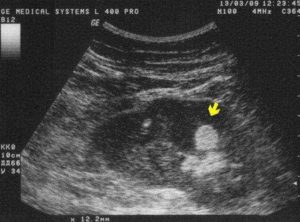

Метод УЗ-исследования основан на степени отражения ультразвука от тканей различной плотности. Гиперэхогенность – это усиление акустической тени, то есть на практике это значит, что структура органа имеет высокую плотность и хорошо отражает ультразвук. На мониторе это выглядит как более светлая, почти белая область.

Синдром белых пирамидок в почках наблюдается и в норме, например, у худощавых людей до 30–40 лет, подростков. Но часто он указывает на образование включений при метаболических нарушениях обмена, приеме некоторых лекарственных препаратов, например, Фуросемида, гормональных веществ. Также он может присутствовать при гиперфункции щитовидной железы, гипервитаминозе D.

При болезнях почек на УЗИ часто обнаруживают синдром гиперэхогенных пирамид, рассмотрим, что это такое. Если структура пирамидок поражена, изменяется ее эхогенность. Причиной повышения является образование включений (камни, песок), новообразований, или воспалительный процесс.

Например, симптом гиперэхогенных пирамид может быть при остром пиелонефрите, за счет инфильтрации почек лейкоцитами. Также повышение плотности наблюдается при образовании кальцификатов, отложении солей.

Затем рассматривается структура и строение паренхимы. Появление крупных образований высокой плотности вызвано образованием камней при мочекаменной болезни или развитием очагового воспалительного процесса.

Особое внимание надо обратить на яркие, белые включения, которые указывают на наличие в почках склеротической ткани, кальцификатов и псаммомных телец (белково-жировые комплексы), присущих злокачественным новообразованиям.